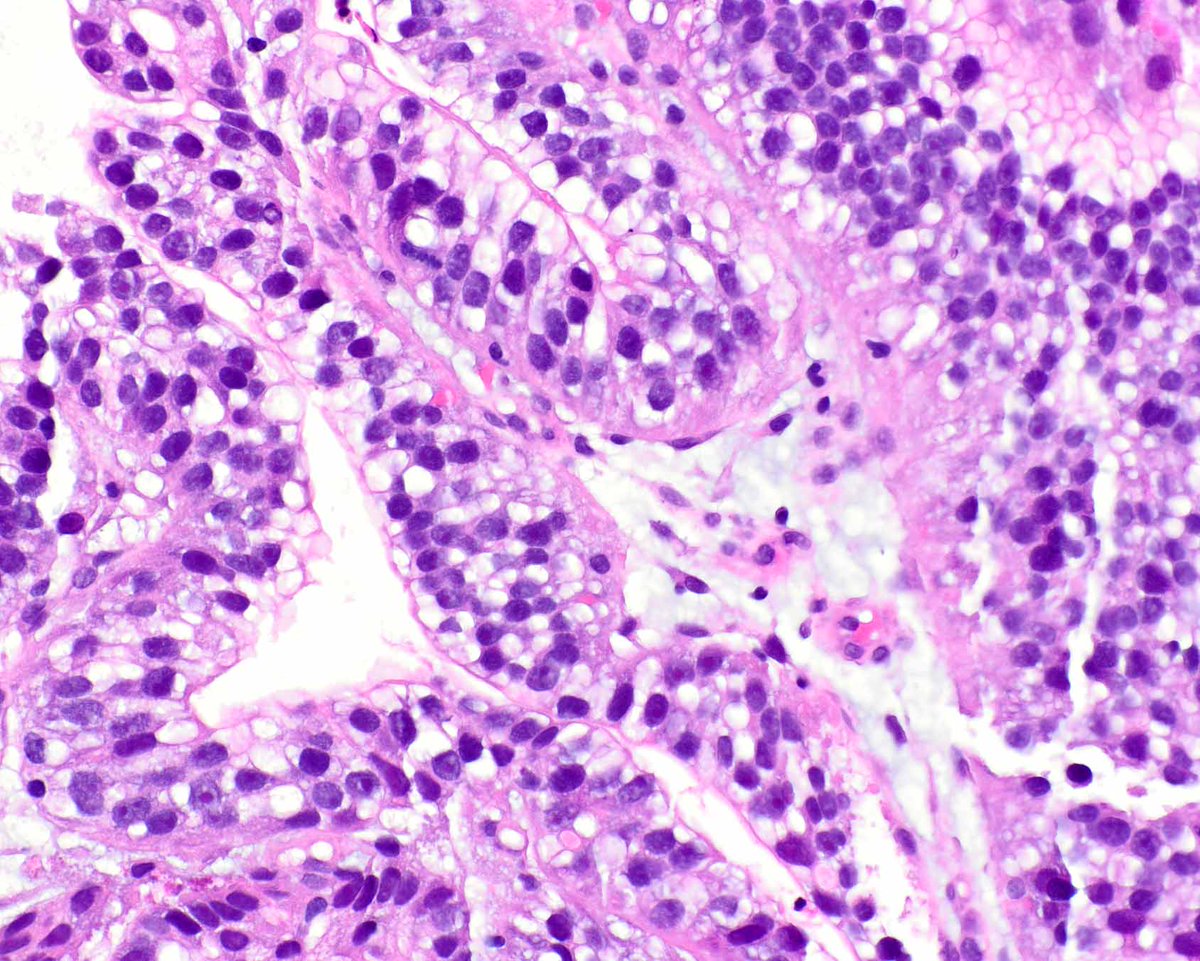

Our GI Pathology Fellowship has an unexpected opening for July 2026. Dr. Ortiz (right) and I are the program directors. We have superb cases and excellent colleagues (Drs. M. Garcia, R. Yantiss, S. Al Diffalha, O. McDonald). Send your CV to adriana.zanaty@miami.edu